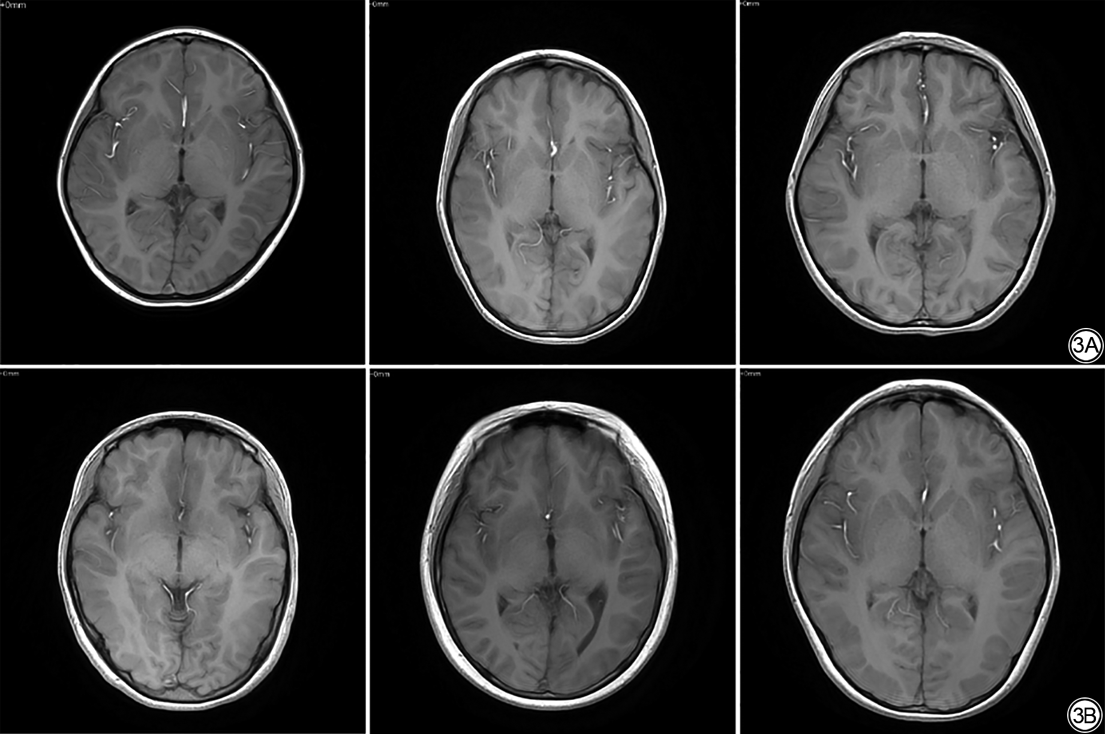

最终1077例纳入研究,男583例,女494例,年龄(5.94±3.85)岁(范围1个月~16岁)。其中经神经内科临床确诊为VE的患儿577例,男312例,女265例,年龄(5.57±3.78)岁(范围1个月~15.67岁)。非VE儿童500例,男271例,女229例,年龄(6.36±3.88)岁(范围1个月~16.17岁)。非VE儿童的MRI检查原因人数分布如图2所示。儿童VE的主要诊断标准为:头痛、发热、嗜睡、认知/行为改变等精神状态异常;出现局部或弥漫性脑炎症状;脑脊液检测结果异常;CT、MRI等脑影像学结果提示异常等并排除由创伤、代谢混乱、肿瘤等非感染性病因引起的疾病[23, 24]。本文是基于临床轴位Fast Field Echo(FFE)T1WI序列图像进行研究,VE患儿与非VE患儿T1WI序列图像如图3所示。

儿童VE是一种常见中枢神经系统感染性疾病,具有高致残率和死亡率的特点,常常难以治愈[1]。现阶段儿童脑炎的诊断主要依赖临床症状、实验室检查(脑脊液检查)、影像学和脑电图检测等方法[24]。然而脑炎患儿早期临床表现不典型,影像学和脑电图检测则只有重症时才能明显观察到病变区域,作为脑炎诊断金标准的脑脊液检查是一种耗时较长的有创技术手段[5],如图3所示,VE患儿与非VE患儿在影像学上表现并无明显差异。这些局限性妨碍了缺乏神经内科专科医生的基层医院对于患儿在发病早期阶段的精准诊断和及时干预,延误了治疗时机,导致患儿致残致死率增加[30]。